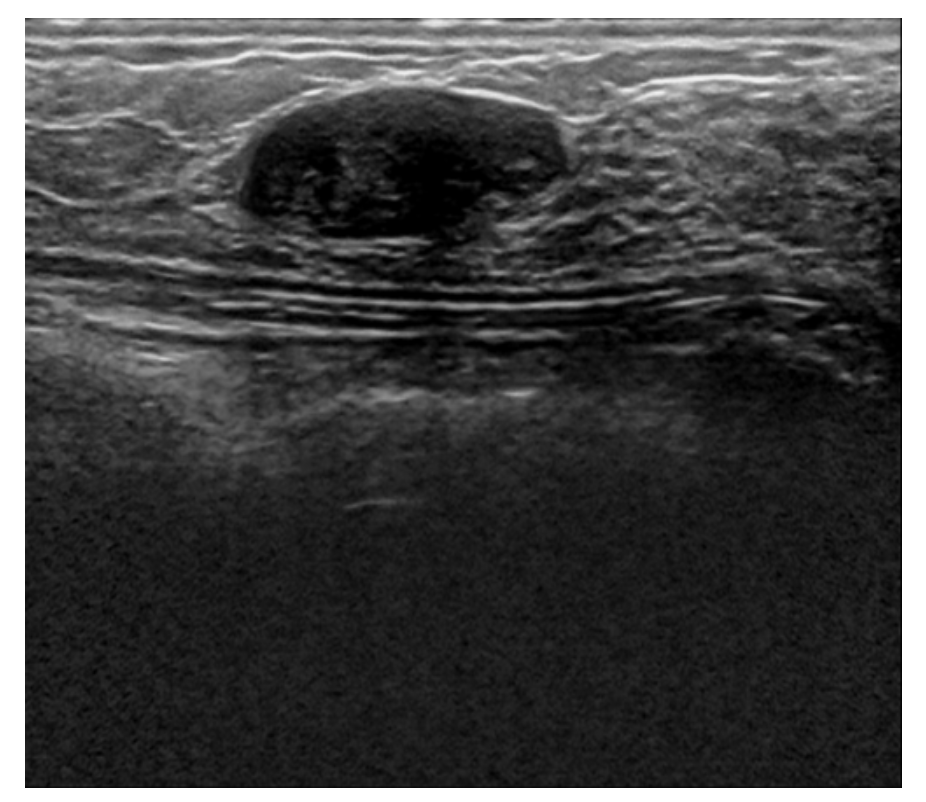

The fourth dataset is Spain Dataset sometimes referred to as Dataset B, which consists of 163 images, however, every image doesn’t have a mask.